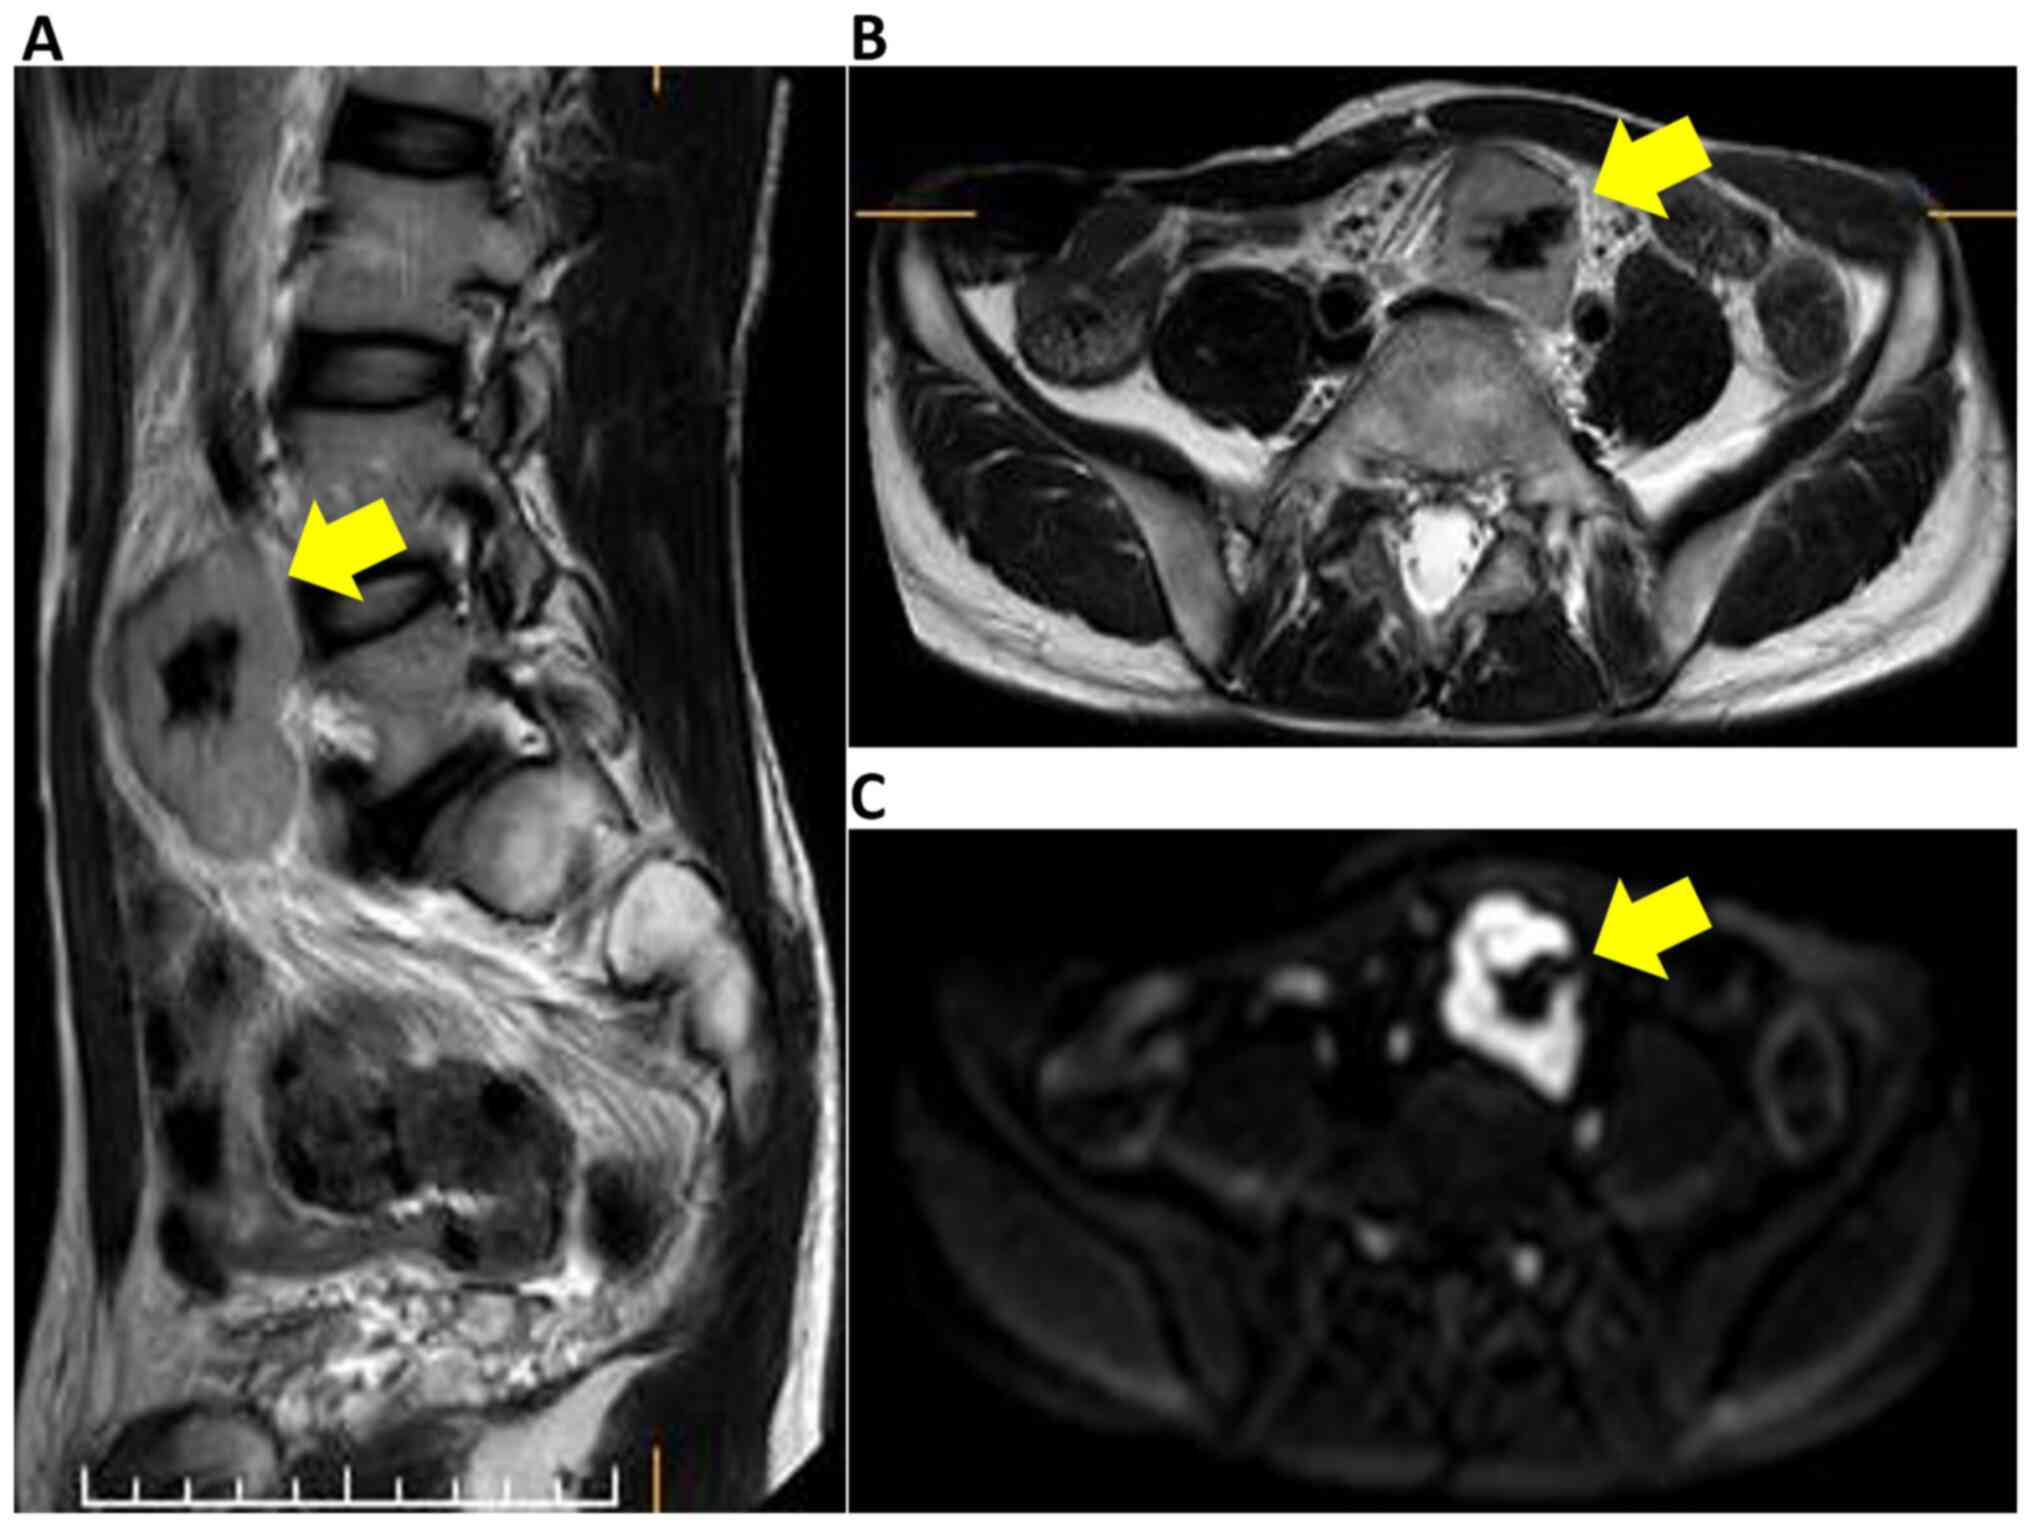

A 44-year-old man presented with a history of diarrhea at another hospital. He was diagnosed with acute enteritis with computed tomography (CT), and the diarrhea was relieved after a few days. The CT scan incidentally revealed a pelvic retroperitoneal mass with calcification, and he was referred to Osaka University Hospital. The patient underwent appendectomy for appendicitis 30 years ago, and had no viral infection or history of any other diseases. The pelvic calcification was previously identified in previous abdominal X-rays, but further examination was not performed. Physical examination revealed no abnormal symptoms. Laboratory blood tests, including for tumor makers (CA19-9 and carcinoembryonic antigen) were normal. Any abnormal finding was not detected by colonoscopy. The abdominal contrast-enhanced CT scan revealed a well-defined 50x30 mm mass behind the sigmoid mesenteric, under the bifurcation of the aorta in the pelvic retroperitoneal. Non-enhanced phase imaging revealed coarse calcification inside the mass, and evident contrast enhancement was observed in the mass during the arterial phase (Fig. 1). Magnetic resonance imaging (MRI) also revealed a well-defined 50x30 mm solid mass situated in the pelvic retroperitoneal. The mass demonstrated heterogeneous and moderately hyperintense signal intensity, and the low signal intensity corresponded to calcification in the T2-weighed images and diffusion-weighted images (Fig. 2). A positive emission tomography/CT scan was performed to exclude the possibility of paraneoplastic manifestations of a primary tumor, and it revealed a 50x30 mm space-occupying lesion with hypermetabolic activity (SUVmax at 4.1) (Fig. 3). Possible differential diagnosis based on the images were CD, primary mesenteric gastrointestinal stromal tumor or leiomyoma. At first, a diagnosis of CD was doubted as the tumor had calcification, exhibited a strong contrast in imaging, had an uniform edge and a relatively uniform inside on the abdominal CT scan; the tumor was generally isointense on T1 weighted images and hyperintense on T2 images (8). Surgical resection following embolization was suggested. Angiographically, the tumor was hypervascular with a dense capillary blush, and it was supplied by the middle sacral artery (Fig. 4). The vasculature of the mass was embolized by DMSO and the patient was operated on the following day.

Pelvic MRI findings. (A) MRI sagittal T2; the arrow shows the 50 mm solid mass with high intensity. (B) MRI axial T2; the arrow points to the high intensity mass with a low intensity lesion. (C) MRI axial diffusion weighted image. The arrow points the mass with high intensity. MRI, magnetic resonance imaging.